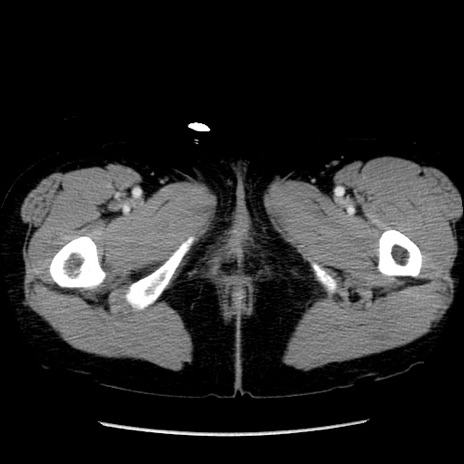

症例6(横断像)

【症例】50歳代女性

【主訴】下腹部痛

【現病歴】本日朝より下痢2回あり。 昼食を食べた後、嘔吐3回、下腹部痛認め、症状軽快せず、当院救急搬送。

最終食事:本日昼(生ものなし)。 昨日の夜、刺身を食ぺたとのこと。周囲に同様の症状の者なし。普段、排便は毎日あるとのこと。

【既往歴】卵巣癌術後(8年前に当院で卵巣摘出)

【身体所見】 意識清明、腹部:平坦、腸蠕動音→、やや硬、下腹部自発痛・圧痛あり、反跳痛あり、筋性防御なし。

【データ】WBC 16000、CRP 0.01